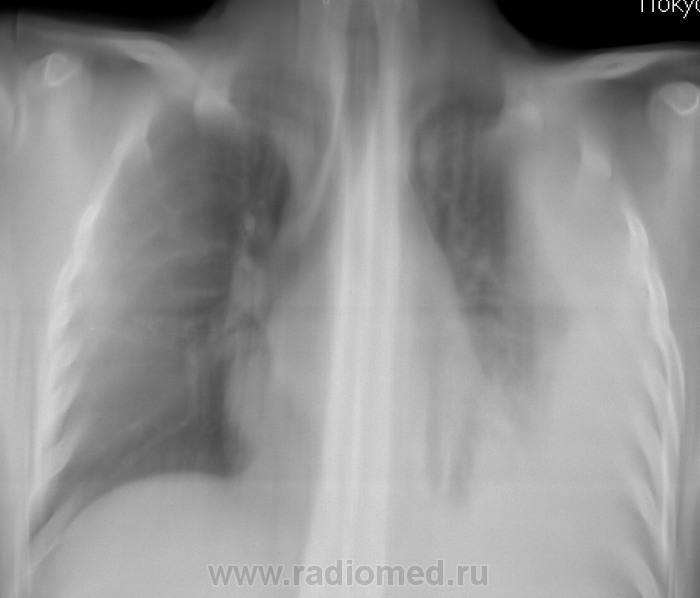

Какие мнения, у уважаемых коллег, будут в плане этиологии, ну и мнения другого плана?

Через 6 месяцев.

Осумкование выпота регрессировало на фоне специфического лечения?

А на последнем, как будто фаза уплотнения.

Этиология туберкулёзная,судя по периодичности снимков.Динамика уверенно положительная.

такие случаи, кажется, называются во фтизиатрии казеома плевры (субплеврально расположенная туберкулома). Очень интересный случай, спасибо большое)

Неоднократные исследования мокроты, посев на жидких средах. Верификация на базе ОПТД.

Нет. Пункции не было.

Но, Его Величество подтверждено.

Наблюдение в течение 2-х лет...

А дело было так. Зацепили мы по "флюшечному контролю" одну "уважаемую" фемину довольно зрелых лет, понятно дообследовали, обнаружили инфильтративный с распадом. Палки были в большом количестве, и была эта фемина "упакована" в областную контору, где с Величеством пытаются бороться...

Потом, конечно фтизиатр начал этот очаг копать.  Очаг оказался большой (именно в данном частном доме) и состоял, в основном из представительниц пола прекрасного, любящих выпить, да и прочим не брезгующих..., так сказать - поклонницы Венус и Бахуса.

Когда коллега фтизиатр, да накинул на эту семейку "мелкий бредень", так оказалось, что из того "кубла" только у одного человека (подросток мужеска пола), на тот момент, Его Величества не было..., а так все..., вплоть до грудного ребёнка...

А пациентке в районе от 20 до 25 лет, да и фейсово, да и фигуристо собой не дурна....

Распад и на КТ обнаружен не был.

В ОПТД делали и бронхоскопию и пункцию

Заключение бронхоскопии: катаральный ( м.б. гнойный) эндобронхит 2 ст. воспаления.Пунктировали несколько раз (2-4) Характер жидкости: получено 100-150 мл прозрачного экссудата светло-желтого цвета , с преобладанием клеток лимфоцитарного ряда.(вкратце)Ну еще может-проба Ривальта++ Ну что,теперь складывается определенная картина и динамика процесса?Легче стало? Nikolas! Эта картина уже сложилась в ОПТД всеми возможными способами. Неужели у Вас- нет? Что тут не ясно?